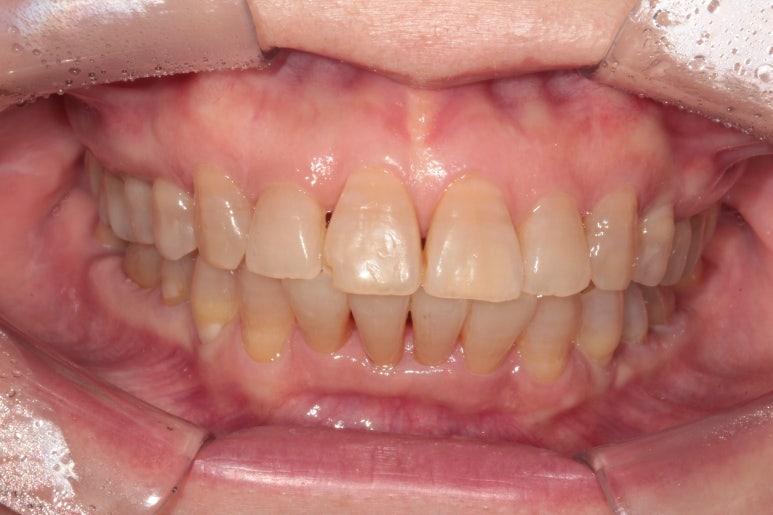

대망의 교정치료 완성의 날.

교정치료가 완성되었습니다!!

비록 앞니가 깨진 것이 조금 눈에 띄긴 하지만... 환자분은 배열만 해도 매우 만족한다 하셔서 이렇게 치료를 마무리 하였습니다. 끝까지 배열이 어려웠던 아래 앞니의 가지런함이 눈에 띕니다.

교합평면도 평평하게 조화롭게 완성된 것을 보실 수 있습니다.

생각보다 평평한 교합평면을 달성해내는 것은 어려운 과정입니다.

교정치료가 끝나고 2년 뒤 내원하셨을 때의 구강내 사진입니다.

스크롤을 위아래로 이동해가며 보시면 아시곘지만, 치열의 변화가 거의 없어요!

성인 앞니 부분교정 2년이 지나고 나서도 변함없이 깔끔하게 유지되고 있는 위턱아래턱 관계를 보실 수 있을거에요. 이렇게 관리 잘 해주시는 분들께 치과의사도 감사함 뿐입니다!

한 개의 크라운도 없이 오직 치아배열만으로 비교적 짧은 시간에 치료를 마칠 수 있었던 성인교정 케이스였습니다.